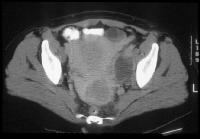

Stage Ib carcinoma confined to the cervix. CT image shows a mass with slightly heterogeneous area of attenuation expanding the cervix and surrounded by a thin rim of relatively preserved stroma. The cervical margins are smooth, well defined, and intact. Parametrial soft-tissue stranding or masses are lacking, and the periureteral fat planes are preserved. Cervix, cancer. CT image depicts a large lobulated mass replacing the cervix and showing non-uniform hypoattenuation. The air and fluid in the center of the mass are consistent with tumor necrosis and complicating infection (the patient had purulent discharge). The central hypoattenuation in the uterine corpus is suggestive of minimal fluid in the cavity.